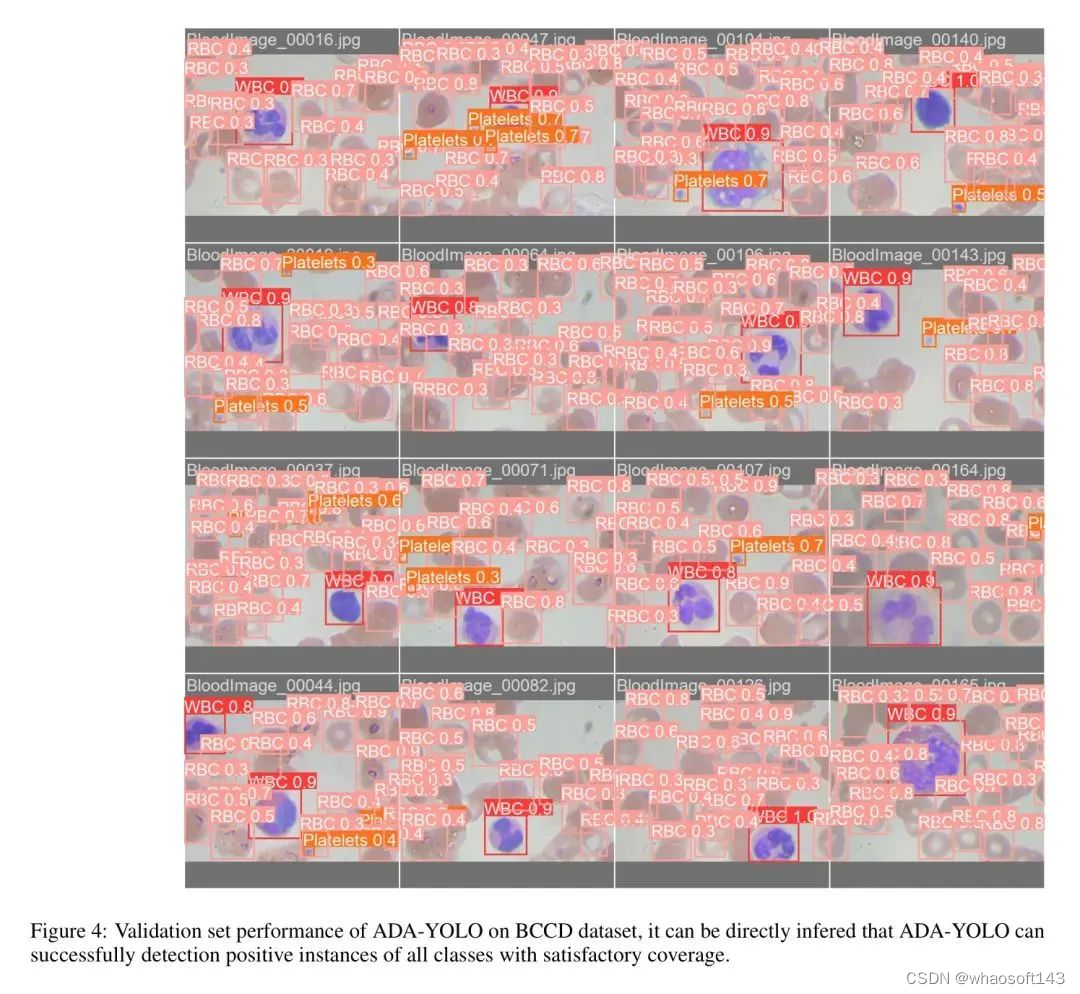

2.0 ADA-YOLO

一种内存高效的 ADA-YOLO 模型,该模型利用新颖的架构和训练策略来增强医学图像中多目标检测的鲁棒性。通过在各种数据集上的实验,证明了 ADA-YOLO 在处理医学图像中的遮挡相关挑战方面具有优越性能。模型在准确局部化和分类多个目标方面,即使在遮挡条件下也表现出卓越性能。YOLOv8+注意力+Adaptive Head,相对YOLOv8,mAP提升3%+118FPS

为了解决这个问题,作者提出了一种名为ADA-YOLO的轻量级但有效的医学目标检测方法,该方法将注意力机制与YOLOv8架构相结合。作者提出的这种方法通过自适应头模块利用动态特征定位和并行回归进行计算机视觉任务。

作者在BCCD(血液细胞计数和检测)数据集上进行了实证实验,以评估ADA-YOLO的有效性。结果表明,在BCCD数据集上,与YOLOv8相比,ADA-YOLO在mAP(平均平均精确率)方面取得了更好的性能,而所需的资源比YOLOv8少3倍以上。这表明作者提出的这种方法是有效的。

ADA-YOLO 模型针对医学影像中的多目标检测,解决了物体遮挡或截断等在医学影像中常见的挑战性问题。如图 4 所示,提出的检测方法可以成功检测到任何大小的红细胞缺失,与基准相比是一个很大的改进。ADA-YOLO 在所有类别中具有 0.918 的召回率,优于基准。

结果展示了 ADA-YOLO 在医学目标检测中揭示更多阳性实例的能力。通过更准确地识别出更高的真实阳性病例比例,即使存在遮挡,作者的模型也能显著提高疾病检测,减少诊断错误,并可以转化为更早、更准确的诊断。